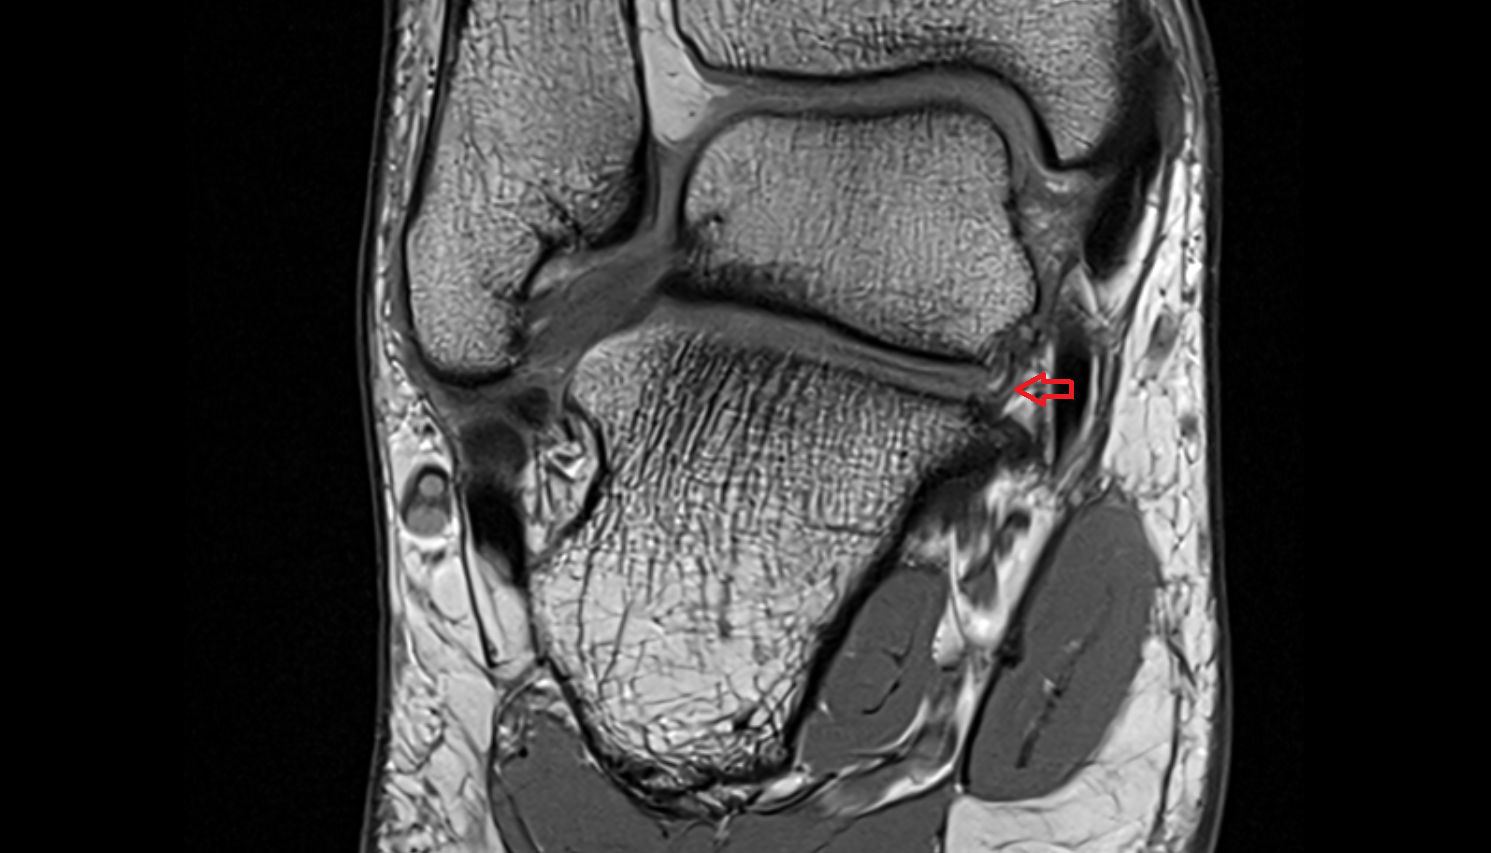

- Temporomandibular joint

- Articular disc of temporomandibular joint

- Articular eminence

- Mandibular condyle

- Mandibular fossa